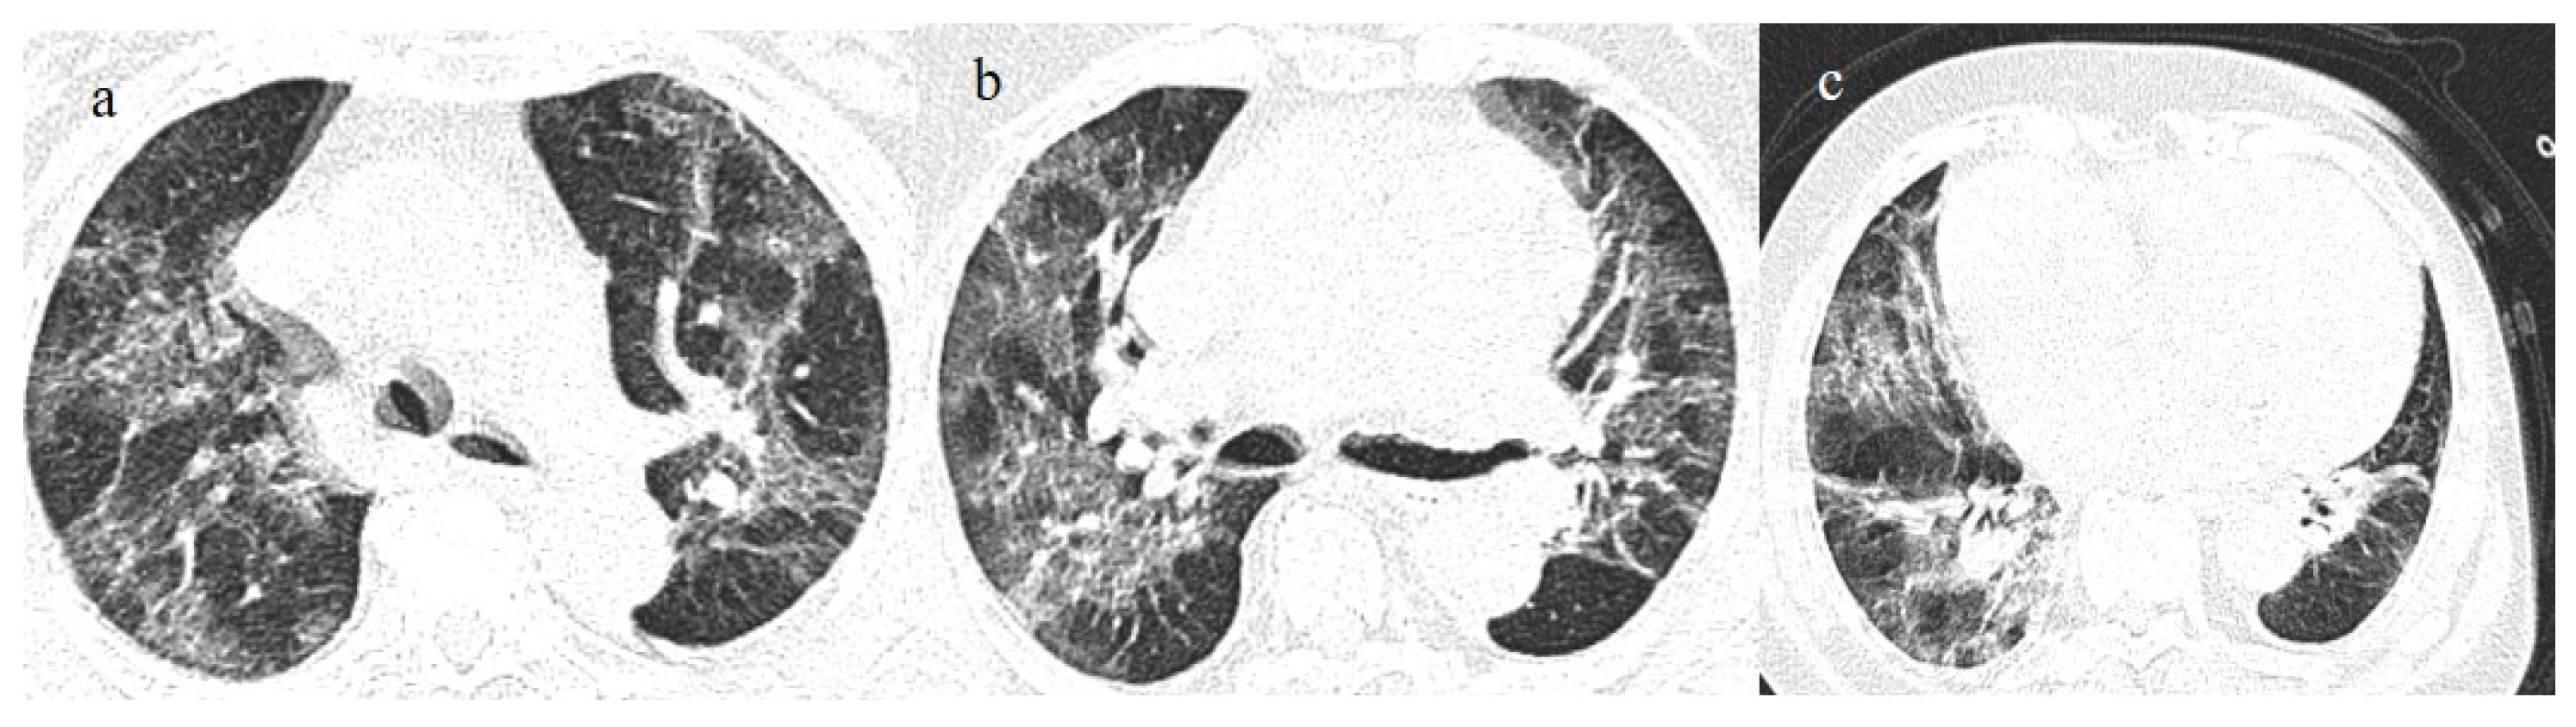

| Indeterminate appearance | Omicron variant | Ito et al., 2022 [54] | Cluster-like GGOs in the Omicron wave. |

| Atypical appearance | Omicron Variant | Hang et al., 2023 [75] | Patients infected with the Omicron variant presented a significantly higher prevalence of nodules, tree-in-bud patterns, and halo signs than patients with the original strain. |

| Ito et al., 2022 [54] | Prevalence of non-peripheral distribution with random distribution during the Omicron wave. | ||

| Lee et al., 2023 [28] | Peribroncovascular pneumonia with the Omicron variant and lower rates of severe pneumonia than the Delta variant. | ||

| Tsakok et al., 2023 [77] | Patients with an Omicron infection presented a greater frequency of bronchial wall thickening but less severe disease compared with the Delta variant. | ||

| Yang et al., 2022 [78] | Only 1.3% of patients infected with the Omicron variant had foci of pneumonia, and the GGOs were unilateral and centrilobular. | ||

| Yoon et al., 2023 [69] | Peribroncovascular GGOs or centrolobular foci during the Omicron wave with less extensive pneumonia. |